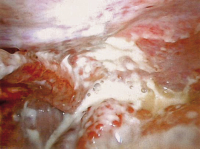

Therapie der Sigmadivertikulitis in den Hinchey-Stadien I und II - ist die laparoskopische Resektion mit primärer Anastomosierung ein geeignetes Verfahren?

Journal für Gastroenterologische und Hepatologische Erkrankungen 2007; 5 (4): 7-12 Volltext (PDF) Summary Abbildungen